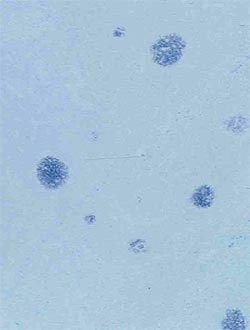

| Isolement viral ** | Permet de détecter le PCV2 (virus viable) qui est isolé dans une culture cellulaire permissive |

** N'est pas utilisé en routine, et de peu d'intérêt diagnostique depuis qu’il a été démontré que l’ADN nu du virus est infectieux une fois introduit dans un tissu permissif.